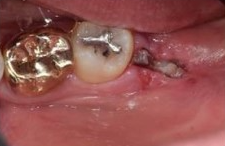

아래 케이스를 보면 위아래 사랑니가

정상 맹출되었으나 충치가 진행되어

주변치까지 영향을 주기 전에

발치를 진행하였습니다.

✅발치 전과 그 다음날

사랑니 발치 전과 그 다음날입니다.

절개하여 발치한 부위를 실밥으로

봉한 모습이 보입니다.

발치전 / 다음날